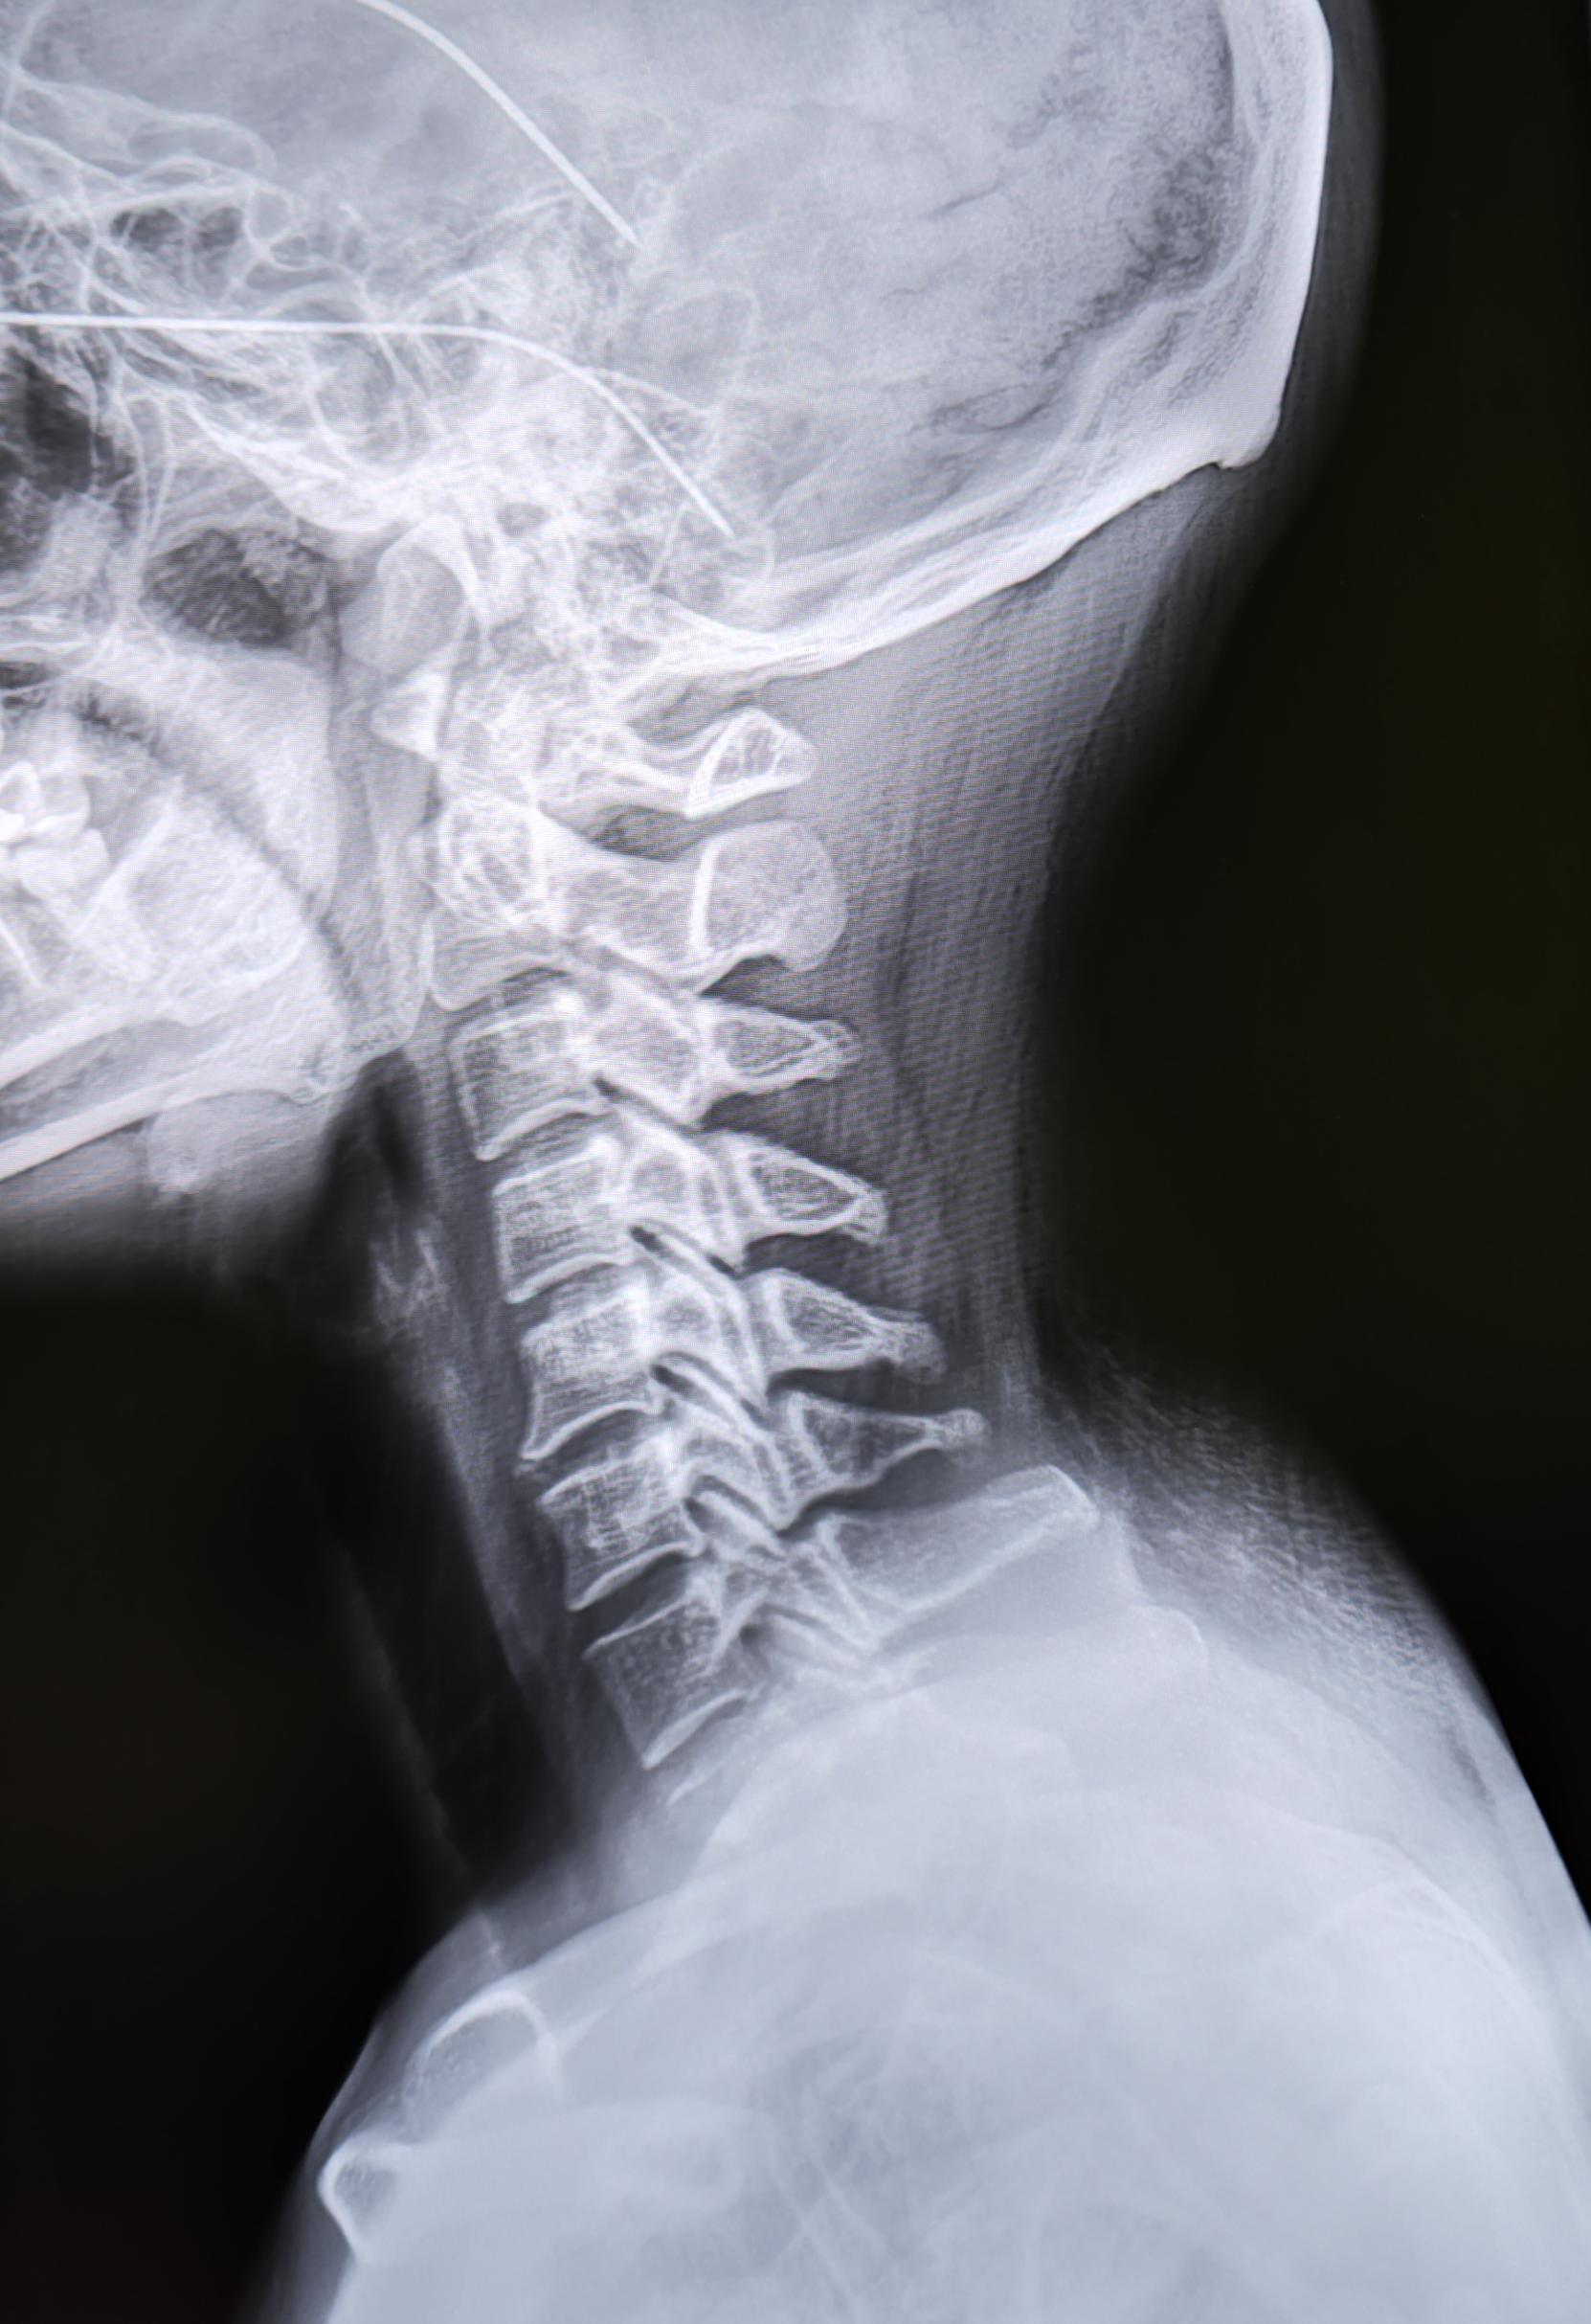

Пациентка (34года) пришла на Р-гр. ШОП, с жалобами на возникшее образование по задней поверхности шеи.